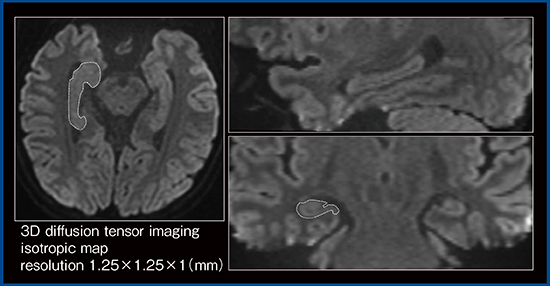

Galan ZGOの特長の一つとして,傾斜磁場コイルの性能の大幅な向上が挙げられる。これにより,従来と同等の画質をより短いecho time(TE)で得ることができる。TEを短縮できれば信号の低下を抑制でき,より高分解能が実現する。標準的な拡散強調画像ではTE=84msであるが,Galan ZGOではTE=60msでの高分解能な拡散強調画像が撮像でき,細部まで描出できるため,海馬の構造を高精度に特定できるようになると考えている(図4)。

図4 Galan ZGOによる高分解能拡散強調画像(3D DTI)での海馬の特定(W.I.P.)